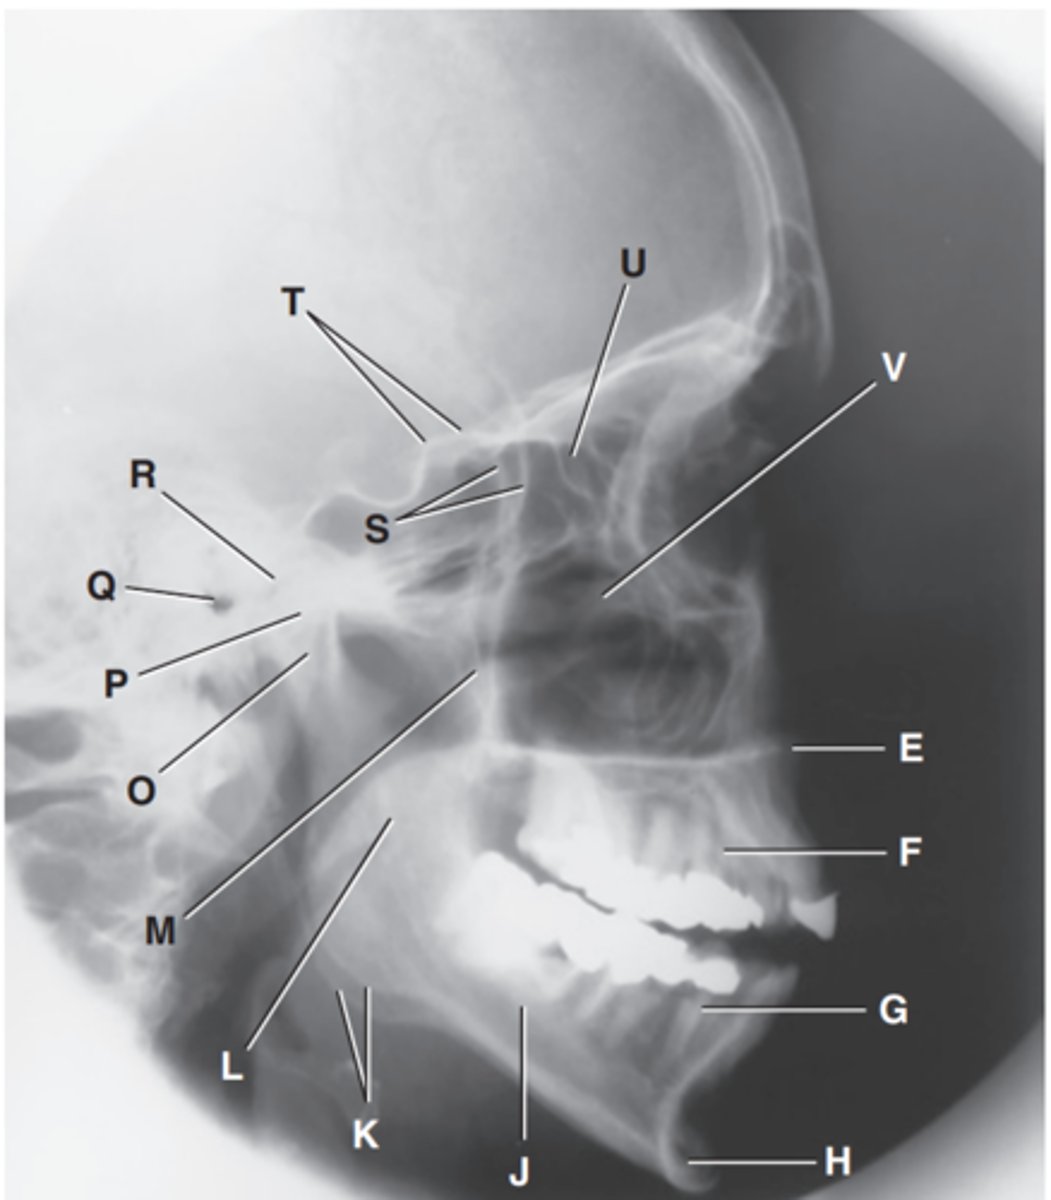

Zygomatic arch

Label A

Right zygomatic bone

Label B

Right nasal bone

Label C

Frontal process of right maxilla

Label D

Anterior nasal spine

Label E

Alveolar process of maxilla

Label F

Alveolar process of mandible

Label G

Mentum or mental protuberance

Label H

Mental foramen

Label I

Body of mandible

Label J

Angle (gonion)

Label K

Ramus of mandible

Label L

Coronoid process

Label M

Mandibular notch

Label N

Neck of mandibular condyle

Label o

Condyle or head of mandible

Label P

EAM

Label Q

TM fossa of temporal bone

Label R

Greater wings of sphenoid

Label S

Lesser wings of sphenoid with anterior clinoid processes

Label T

Ethmoid sinuses between orbits

Label U

Body of maxilla containing maxillary sunuses

Label V